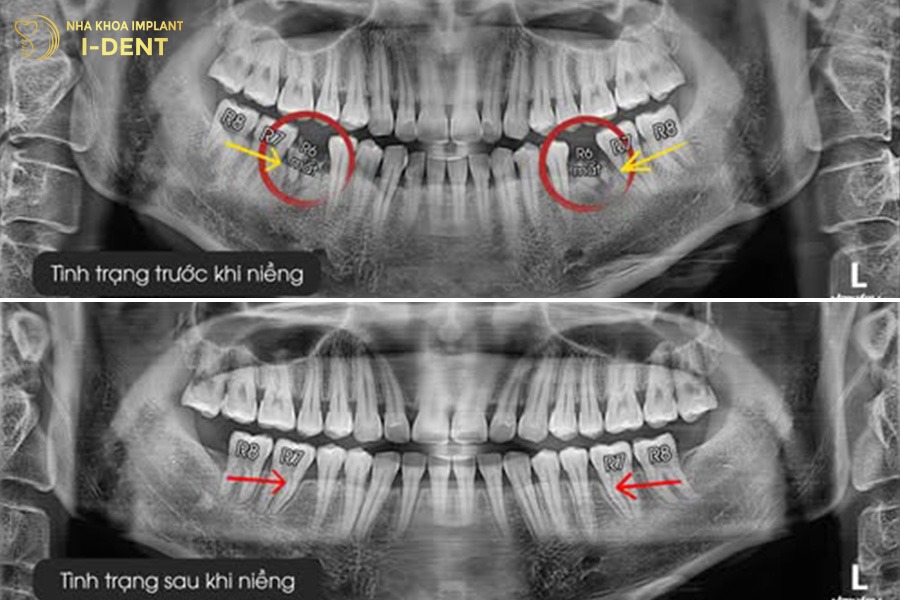

Ở giai đoạn 35 tuổi cấu trúc xương hàm vẫn có khả năng đáp ứng quá trình di chuyển răng nên vẫn có thể sắp xếp răng về đúng vị trí, góc nghiêng trước và sau khi niềng răng có sự cải thiện về mặt thẩm mỹ. Thời gian niềng răng của người trưởng thành chỉ chênh lệch nhẹ so với thanh thiếu niên, trung bình khoảng 18 – 30 tháng tùy tình trạng răng.